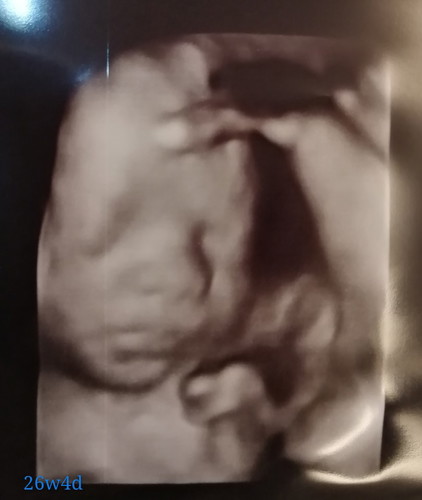

ใครกำหนดคลอด กุมภา เหมือนกันบ้างคับ 26วีคแล้ว ดิ้นเก่งสุดๆ เมื่อวานแม่แอบไปดูหน้ามาคับ

ซาวด์ตอน 24 สัปดาห์ครับ รออีก 10 วันจะได้เจอคนหล่อของแม่อีกที คิดถึงอยากจุ๊บหนูแล้ว 🥰

กุมภาเหมือนกันค่ะ พรุ่งนี้ว่าจะลองซาวด์ 4 มิติดูบ้างแล้วเหมือนกันค่ะ ตอนนี้ 27w 😊